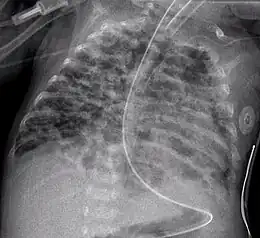

Radiographie thoracique d'un enfant atteint de dysplasie bronchopulmonaire.